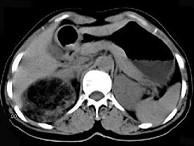

问题 女,53岁,右侧轻度腰背酸痛,行CT检查,如图所示,可能的诊断为()

选项 A.右肾上腺髓样脂肪瘤 B.右肾上腺腺瘤 C.右肾上腺嗜铬细胞瘤 D.右腹膜后脂肪瘤 E.右肾血管平滑肌脂肪瘤

答案 A